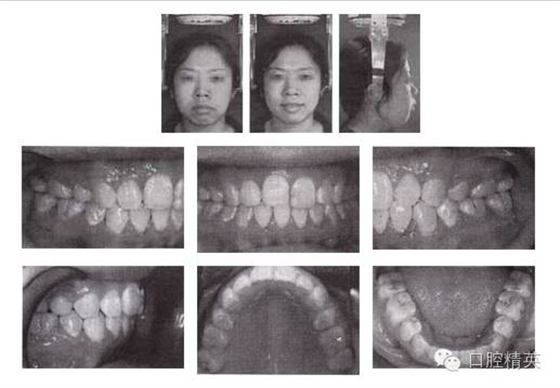

圖3-2 矯治后面像及口內(nèi)像(結束矯治 2005-04-06)

6.矯治結束后,覆頜覆蓋正常,磨牙關系達到中性,后牙直立。